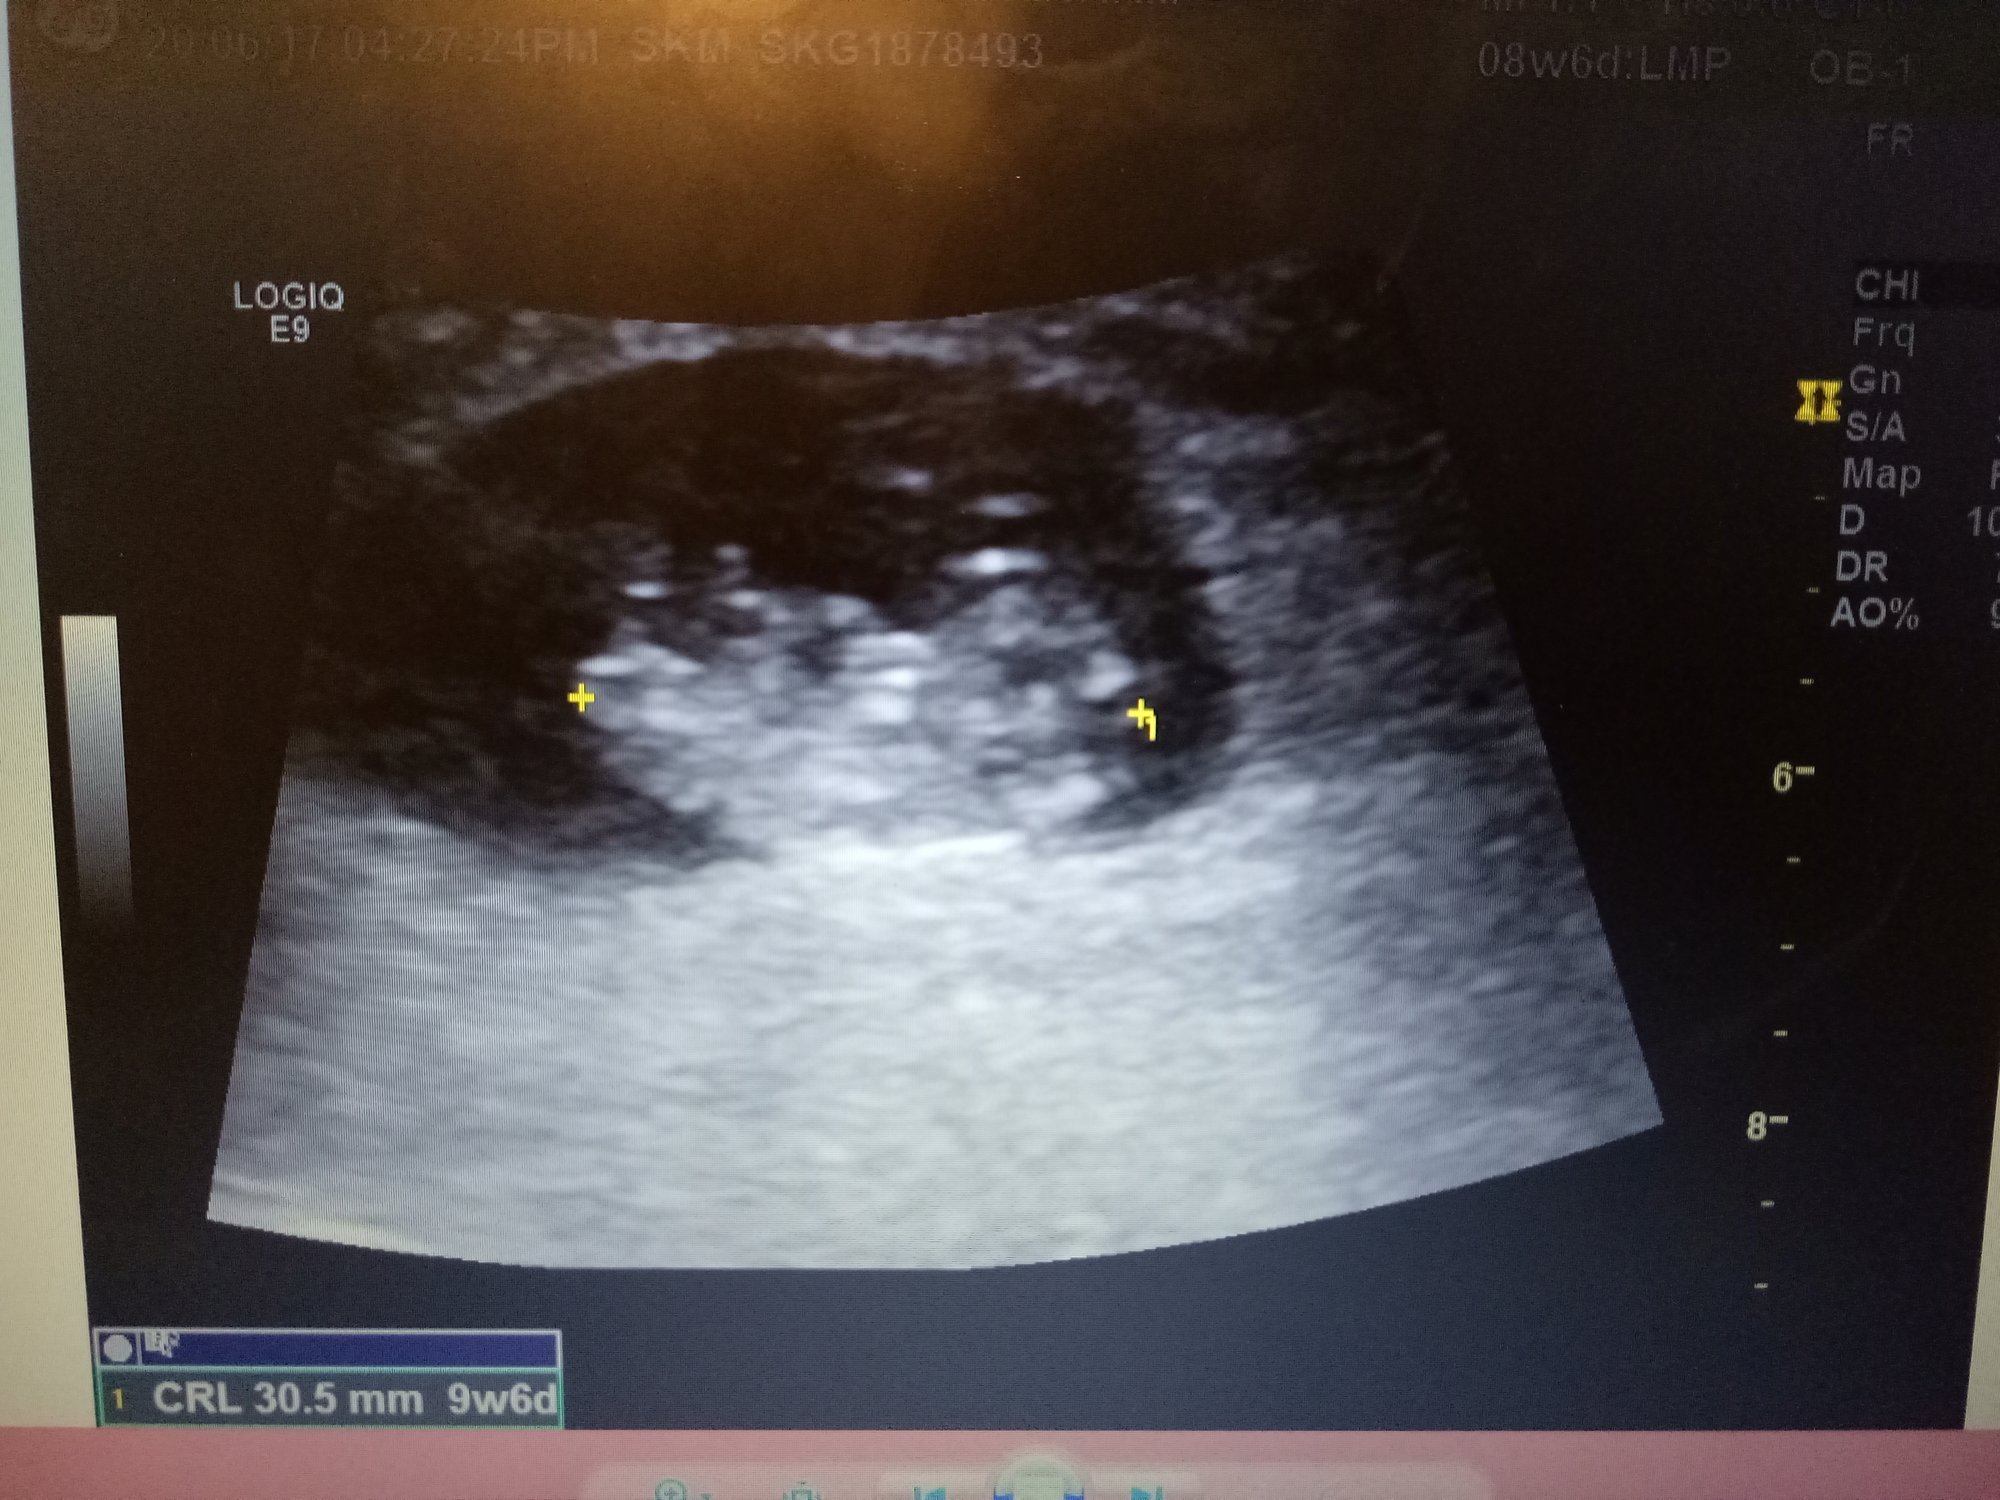

Had this ultrasound on Tuesday at 9w6d and was just wondering what you all think my little poppyseed will be, boy or girl. Healthy heart rate at 173bpm which I know leans towards girl however, looking for some opinions based on the ultrasound

Finding out the sex in a few weeks as I just had the harmony test done. Just want him/her to be healthy and safe in there